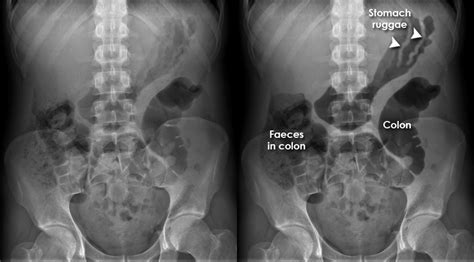

Chest X-rays are commonly used to: * Diagnose and monitor lung diseases, such as pneumonia or lung cancer * Evaluate the size and shape of the heart * Check for injuries or deformities of the chest wall and ribs * Monitor the progression of diseases, such as cystic fibrosis or tuberculosis * Evaluate the effectiveness of treatments, such as antibiotics or chemotherapy